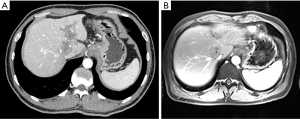

No patient in either treatment group had a CR according to mRECIST (Table 2). In total, 5 (19.2%) patients in the apatinib group versus 1 (2.2%) patient in the sorafenib group had a PR (P=0.012); 10 (38.5%) patients in the apatinib group versus 22 (47.8%) patients in the sorafenib group had a SD (P=0.442); 11 (42.3%) patients in the apatinib group versus 23 (50%) patients in the sorafenib group had a PD (P=0.530); and 15 (57.7%) patients in the apatinib group and 23 (50%) patients in the sorafenib group achieved disease control (P=0.530). (Representative images in Figures 2 and 3).